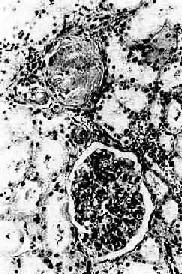

高血压病之肾

图8-12 高血压病之肾

肾小球入球小动脉管壁玻璃样变性,肾小球纤维化,玻璃样变